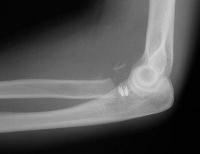

Redisplaced 2 days later:

Click for larger image